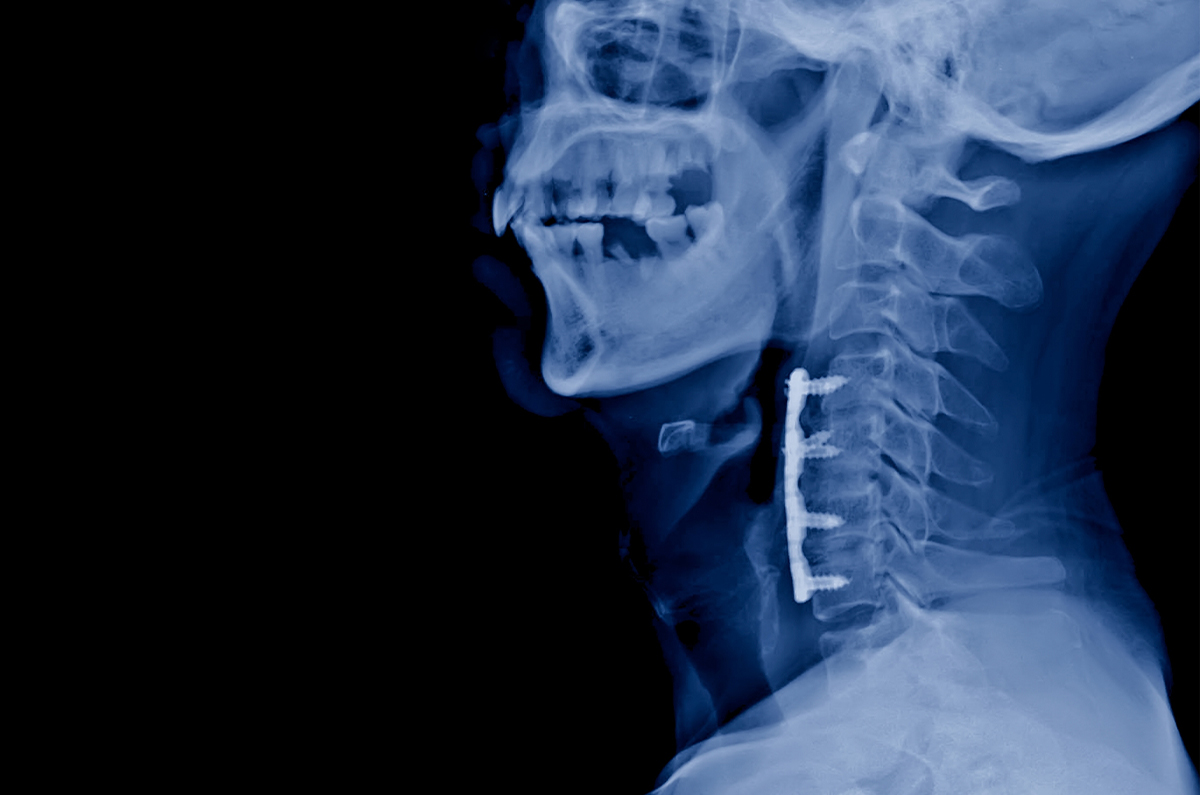

In select cases, cervical spinal fusion can be reversed. If your previous fusion was performed through an anterior approach only (front of the neck), it may be possible to remove the fusion and replace it with an artificial disc. This is known as cervical fusion reversal or fusion-to-disc conversion.

Evaluation includes MRI, CT, and X-rays of the cervical spine, as well as a detailed consultation with Dr. Taghva. Prior surgical records and operative reports are very helpful, as they identify the hardware type and fusion levels that may influence surgical planning.

A small incision is made on the front of the neck, often through the same scar as the original surgery. Scar tissue is carefully released, and the previous hardware and bony fusion are removed using specialized microsurgical tools.

An artificial cervical disc is then inserted in place of the fusion to restore motion at that level.